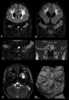

Hunter syndrome, or mucopolysaccharidosis type II (MPS II), is a rare genetic disorder in which large sugar molecules called glycosaminoglycans (or GAGs or mucopolysaccharides) build up in body tissues. It is a form of lysosomal storage disease. [Source: Wikipedia ]